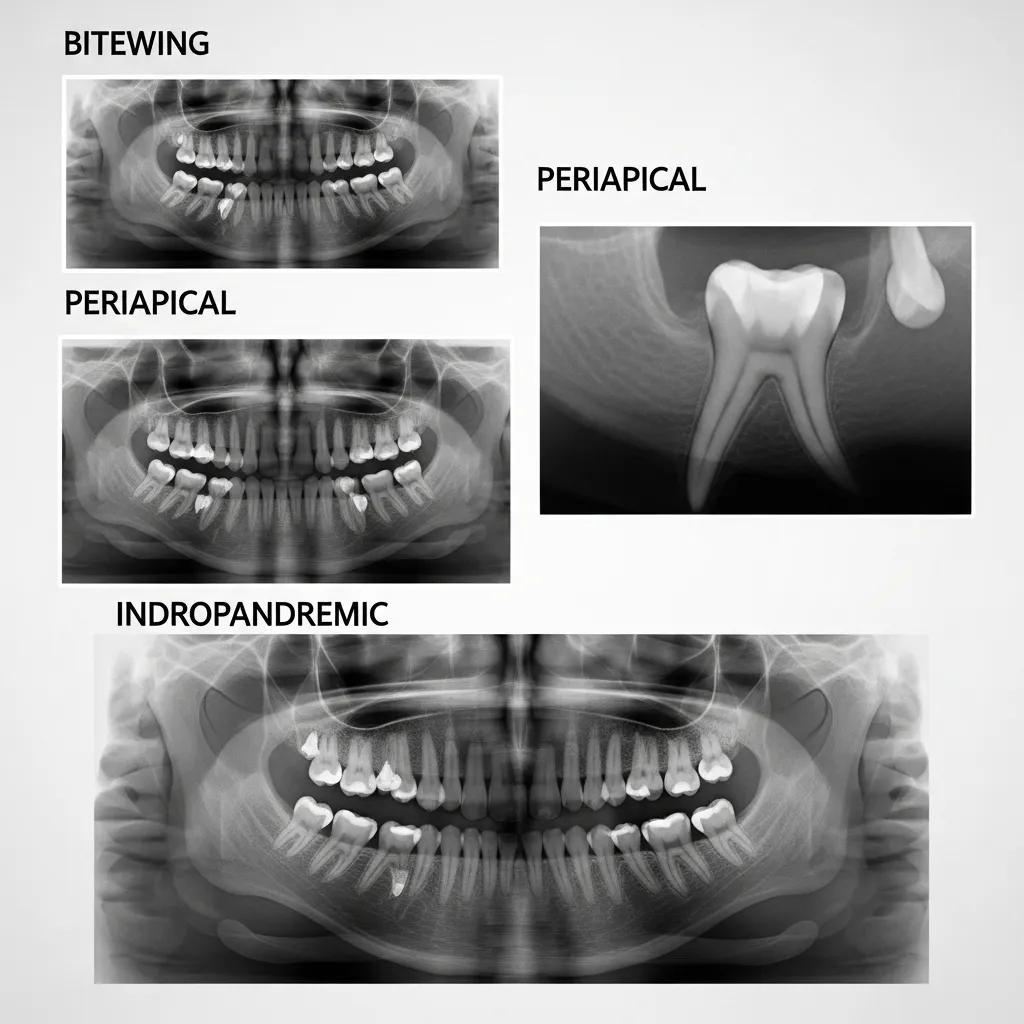

What types of dental X-rays are commonly used?

- Bitewing X-rays: These capture the upper and lower teeth in one area of the mouth, helping to detect cavities between teeth.

- Periapical X-rays: These focus on one or two specific teeth, providing detailed images of the tooth’s root and surrounding bone.

- Panoramic X-rays: These offer a broad view of the entire mouth, including all teeth, jaws, and surrounding structures.